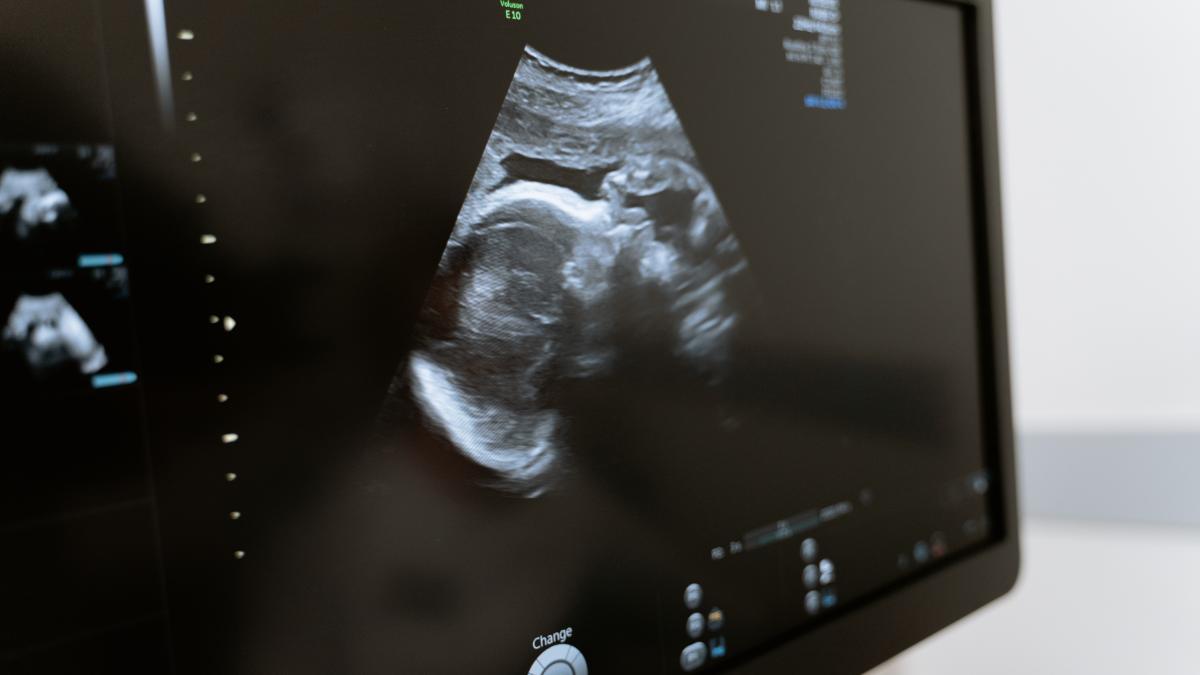

În unele cazuri, avortul intern poate fi asimptomatic și este diagnosticat doar în timpul unui examen medical de rutină sau în timpul unei ecografii care arată absența bătăilor inimii și incapacitatea de creștere a embrionului.

Dacă bănuiți un avort spontan, este important să discutați cu medicul ginecolog cât mai curând posibil. Medicul dumneavoastră poate efectua o examinare cu ultrasunete pentru a confirma diagnosticul și a evalua situația.